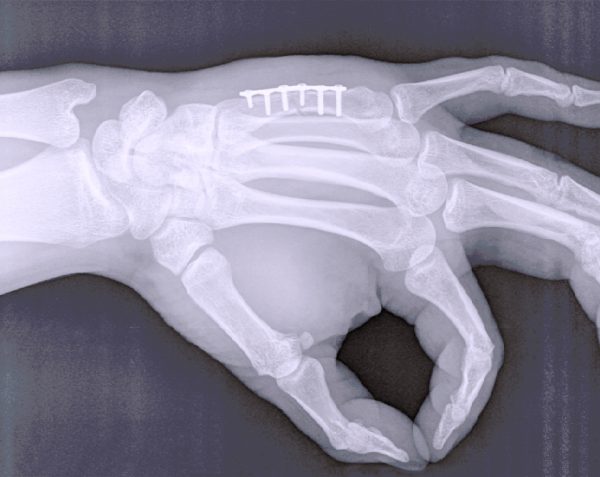

Salud y vida Hospital Angeles Health SystemOsteosíntesis | ¿Qué es y cómo ayuda a tus huesos?Descubre qué es la osteosíntesis, los tipos de implantes disponibles y cómo ayuda a la recuperación de fracturas para mejorar la función y salud de tus huesos.Compartir: